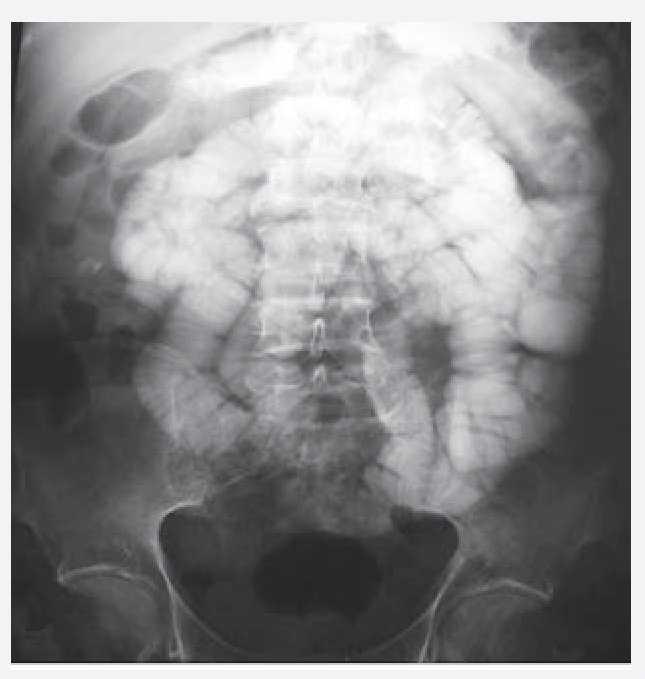

médico conservador. Acudió a consulta por presentar nuevamente dolor en mesogastrio intenso, de 8 horas de evolución, acompañado de vómito de contenido gastrobiliar y distensión abdominal importante. Se le realizó placa simple de abdomen la cual mostró niveles hidroaéreos con dilatación de asas de intestino delgado. Una vez resuelto el cuadro, se realizó tránsito intestinal que mostró dilatación de asas de intestino delgado con predominio de yeyuno (Figura 1). Se le practicó colonoscopia larga observando en íleon terminal, múltiples úlceras serpiginosas de 1 cm, presencia de edema y eritema periférico. La mucosa presentaba apariencia de empedrado alternada con mucosa de características normales (Figuras 2 y 3). Los cortes histológicos mostraron distorsión en la arquitectura a expensas de prolongaciones digitiformes de la lámina propia con inflamación, presencia de polimorfonucleares, eosinófilos y células plasmáticas con ausencia de granulomas, compatible con enfermedad de Crohn (Figura 4). El manejo terapéutico se baso la prescripción de azatioprina y mesalazina con buenos resultados sin presentar recidiva.

Figura 1. Estudio de contraste; tránsito intestinal que mostró dilatación de asas de intestino delgado con predominio de yeyuno